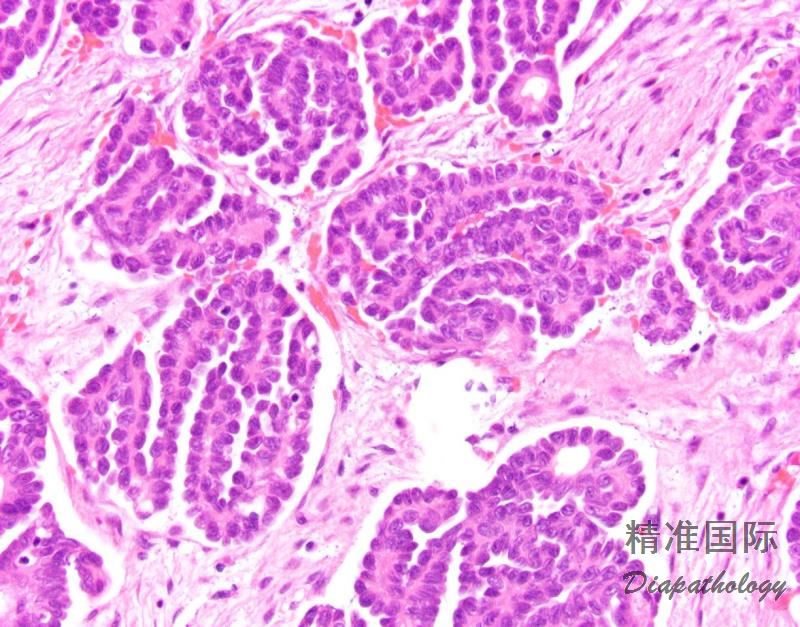

细胞小,形态一致,核多形性不明显,仅轻度-中度异型,具有 1 个明显的核仁;

分裂象少,常小于 3 个/10HPF;

无坏死;

砂粒体常见。